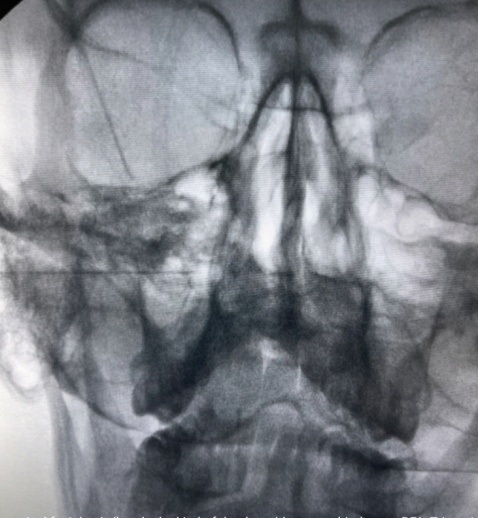

• Block του σφηνουπερώιου γαγγλίου με τοπικό αναισθητικό και κορτιζόνη

• Νευρόλυση του σφηνουπερώιου γαγγλίου με χρήση ραδιοσυχνοτήτων